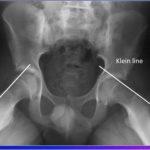

Distal Femur Physeal Fractures

Courtesy: Prof Nabil Ebraheim, University of Toledo, Ohio, USA Distal Femoral Physeal Fractures (Pediatric) Overview Injury to the distal femoral physis in children One of the most important pediatric knee injuries Clinical Importance High risk of growth arrest (~50–60%) Risk increases with: Displacement High-energy trauma Key Clinical Point In children presenting with: Suspected MCL/LCL […]